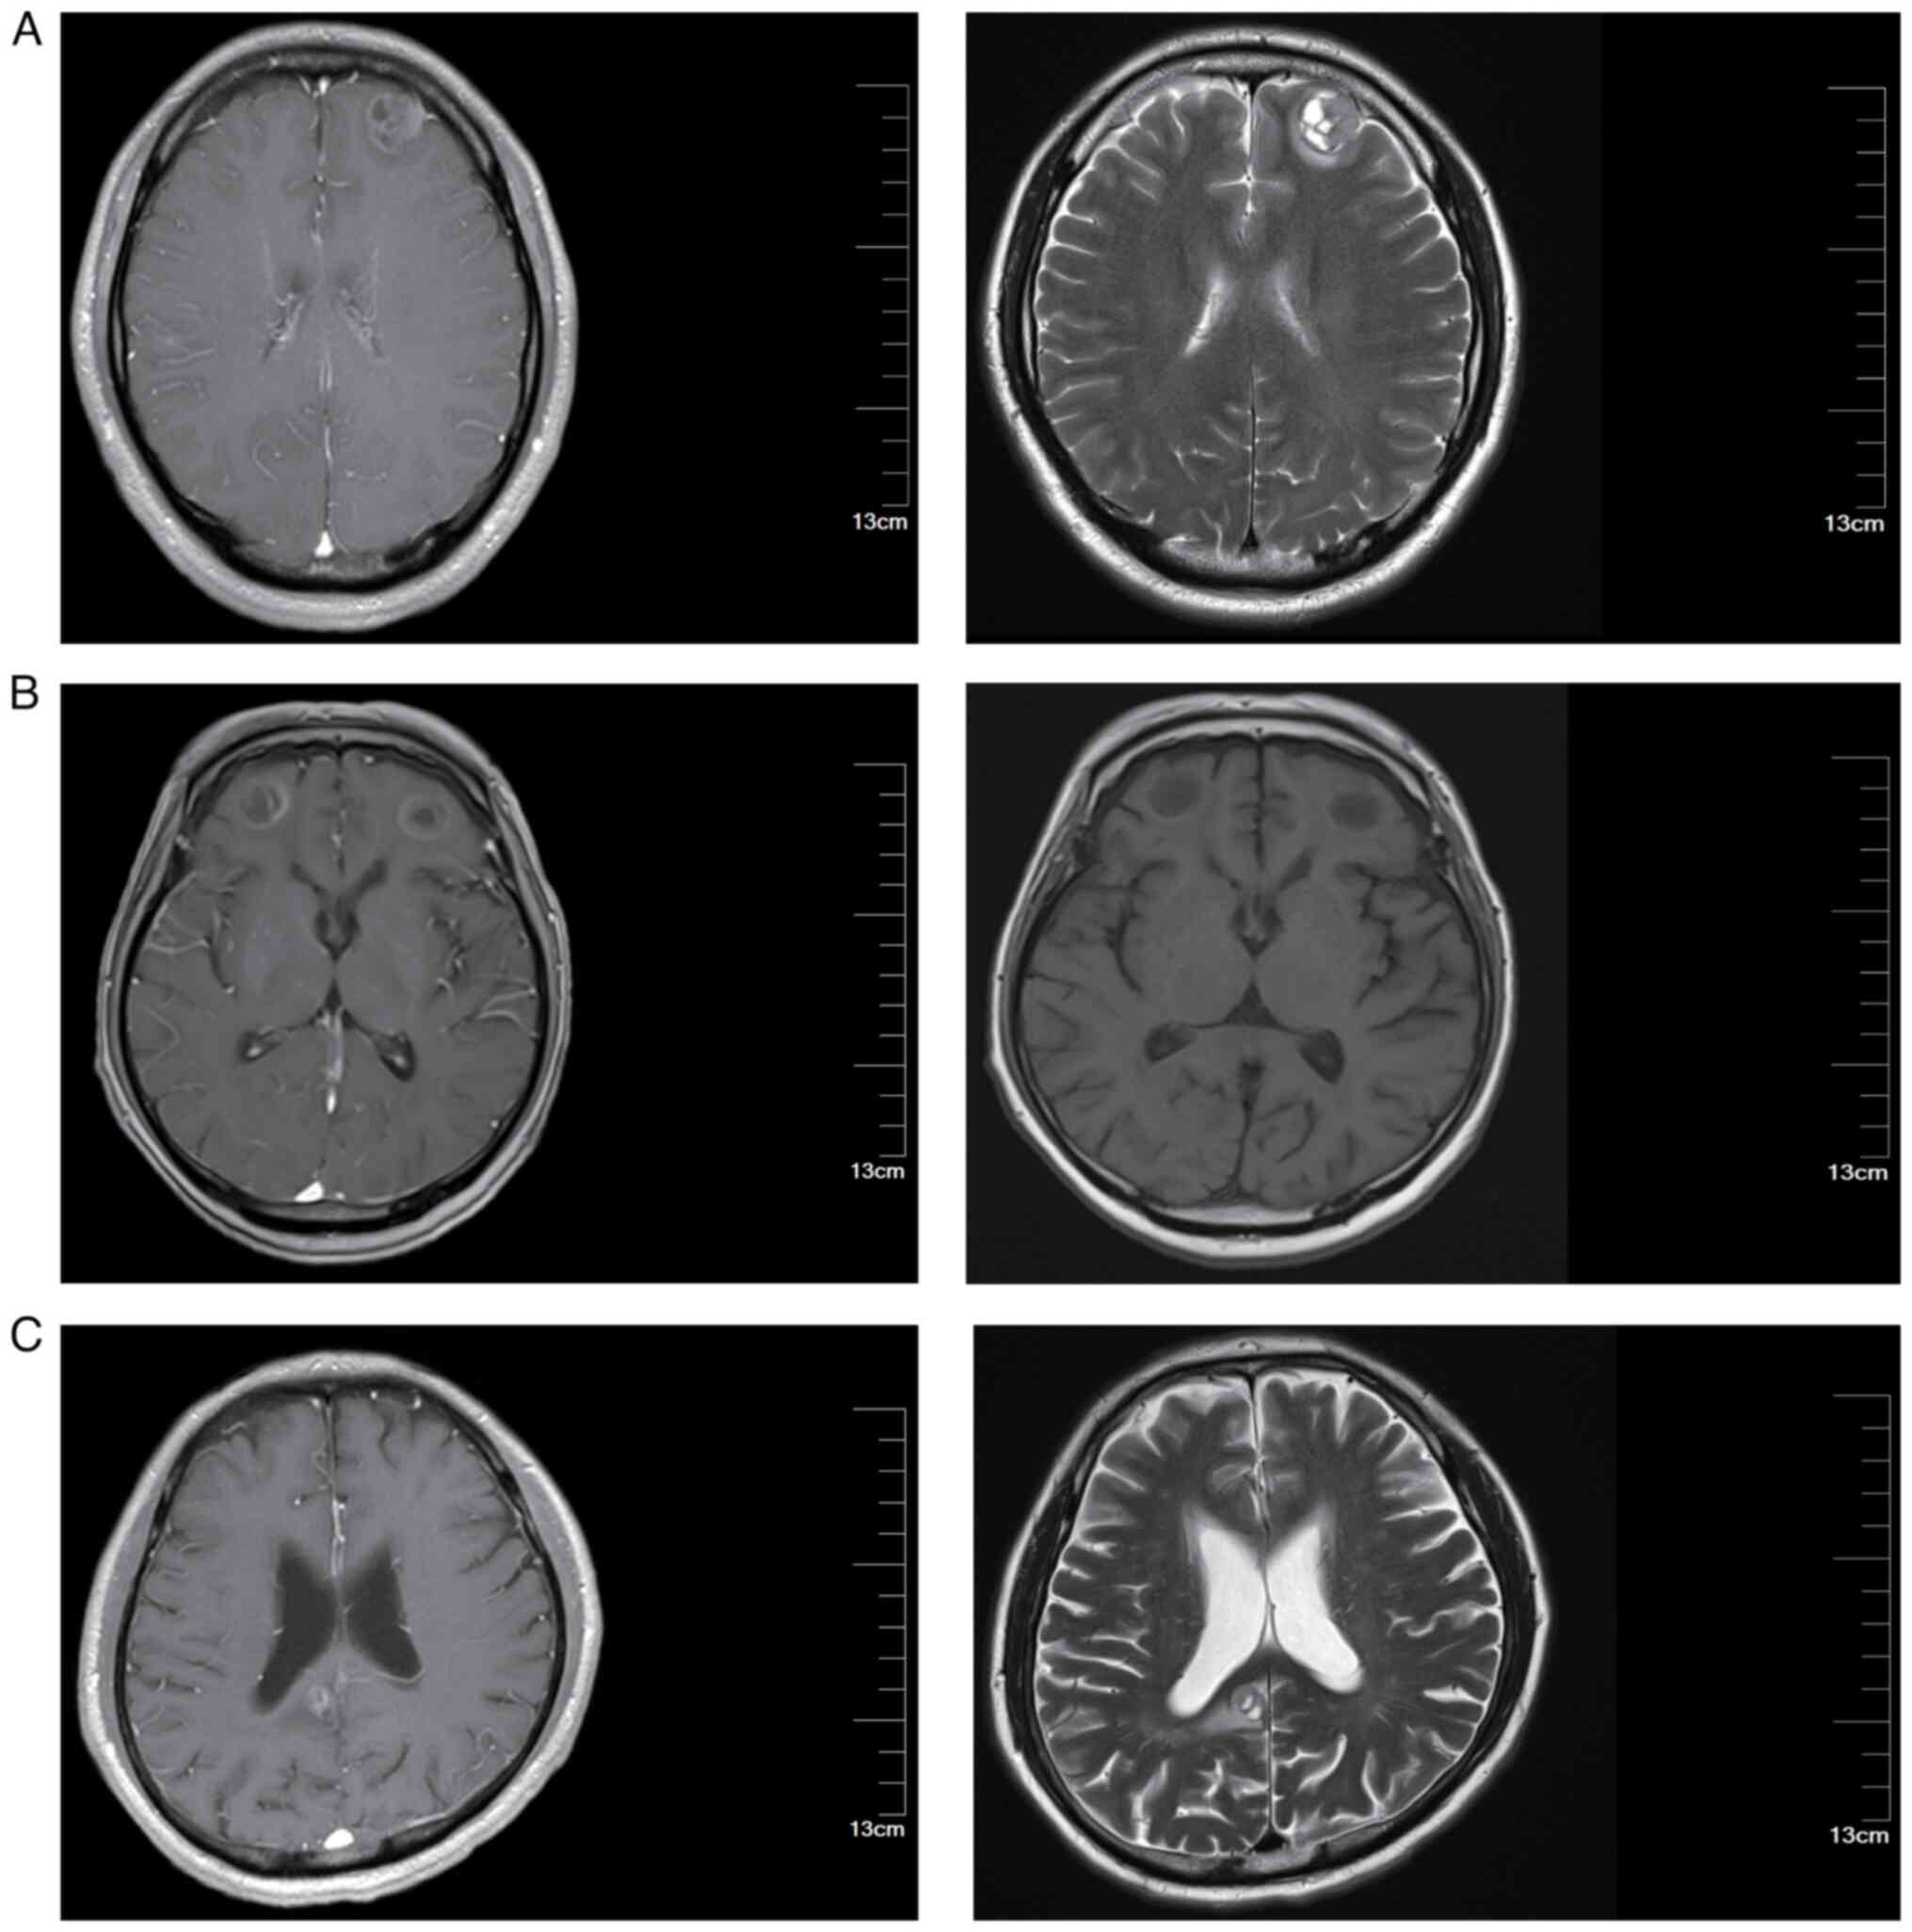

At the time of follow-up, basic clinical data were collected from 290 patients involved in this study. The median age was 58 years, ranging from 42–74 years. A total of 44.5% of these patients (129 cases) presented with an initial tumor diameter of >5 cm at the onset of treatment. The clinical characteristic of the patients are presented in Table I. Representative brain MRI images are shown in Fig. 1. The MRI images presented in this study are representative images taken when brain metastases were first detected in the patients. These images provide a visual representation to help readers better understand the typical appearance and progression of brain metastases in patients with LS-SCLC.